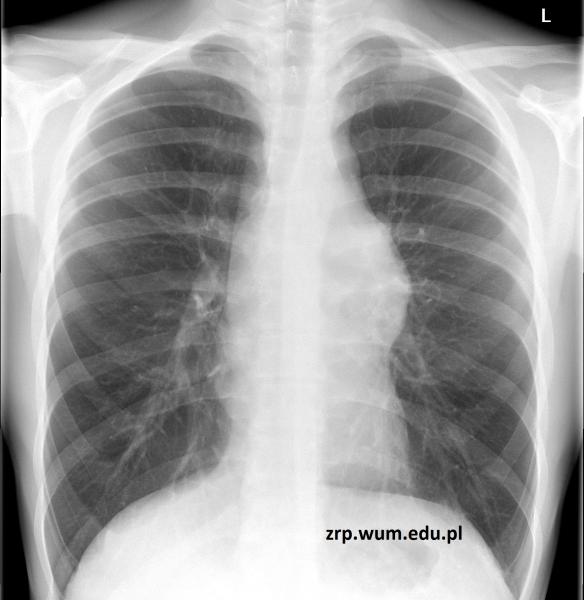

Przypadek 55: 16-letni chłopiec z podejrzeniem guza śródpiersia górnego, wykrytego w kontrolnym badaniu echokardiograficznym.

Rozpoznanie: Na zdjęciu RTG klatki piersiowej stwierdzono poszerzenie cienia śródpiersia po stronie lewej, w rzucie lewej wnęki. W trakcie dalszej diagnostyki rozpoznano chłoniaka.